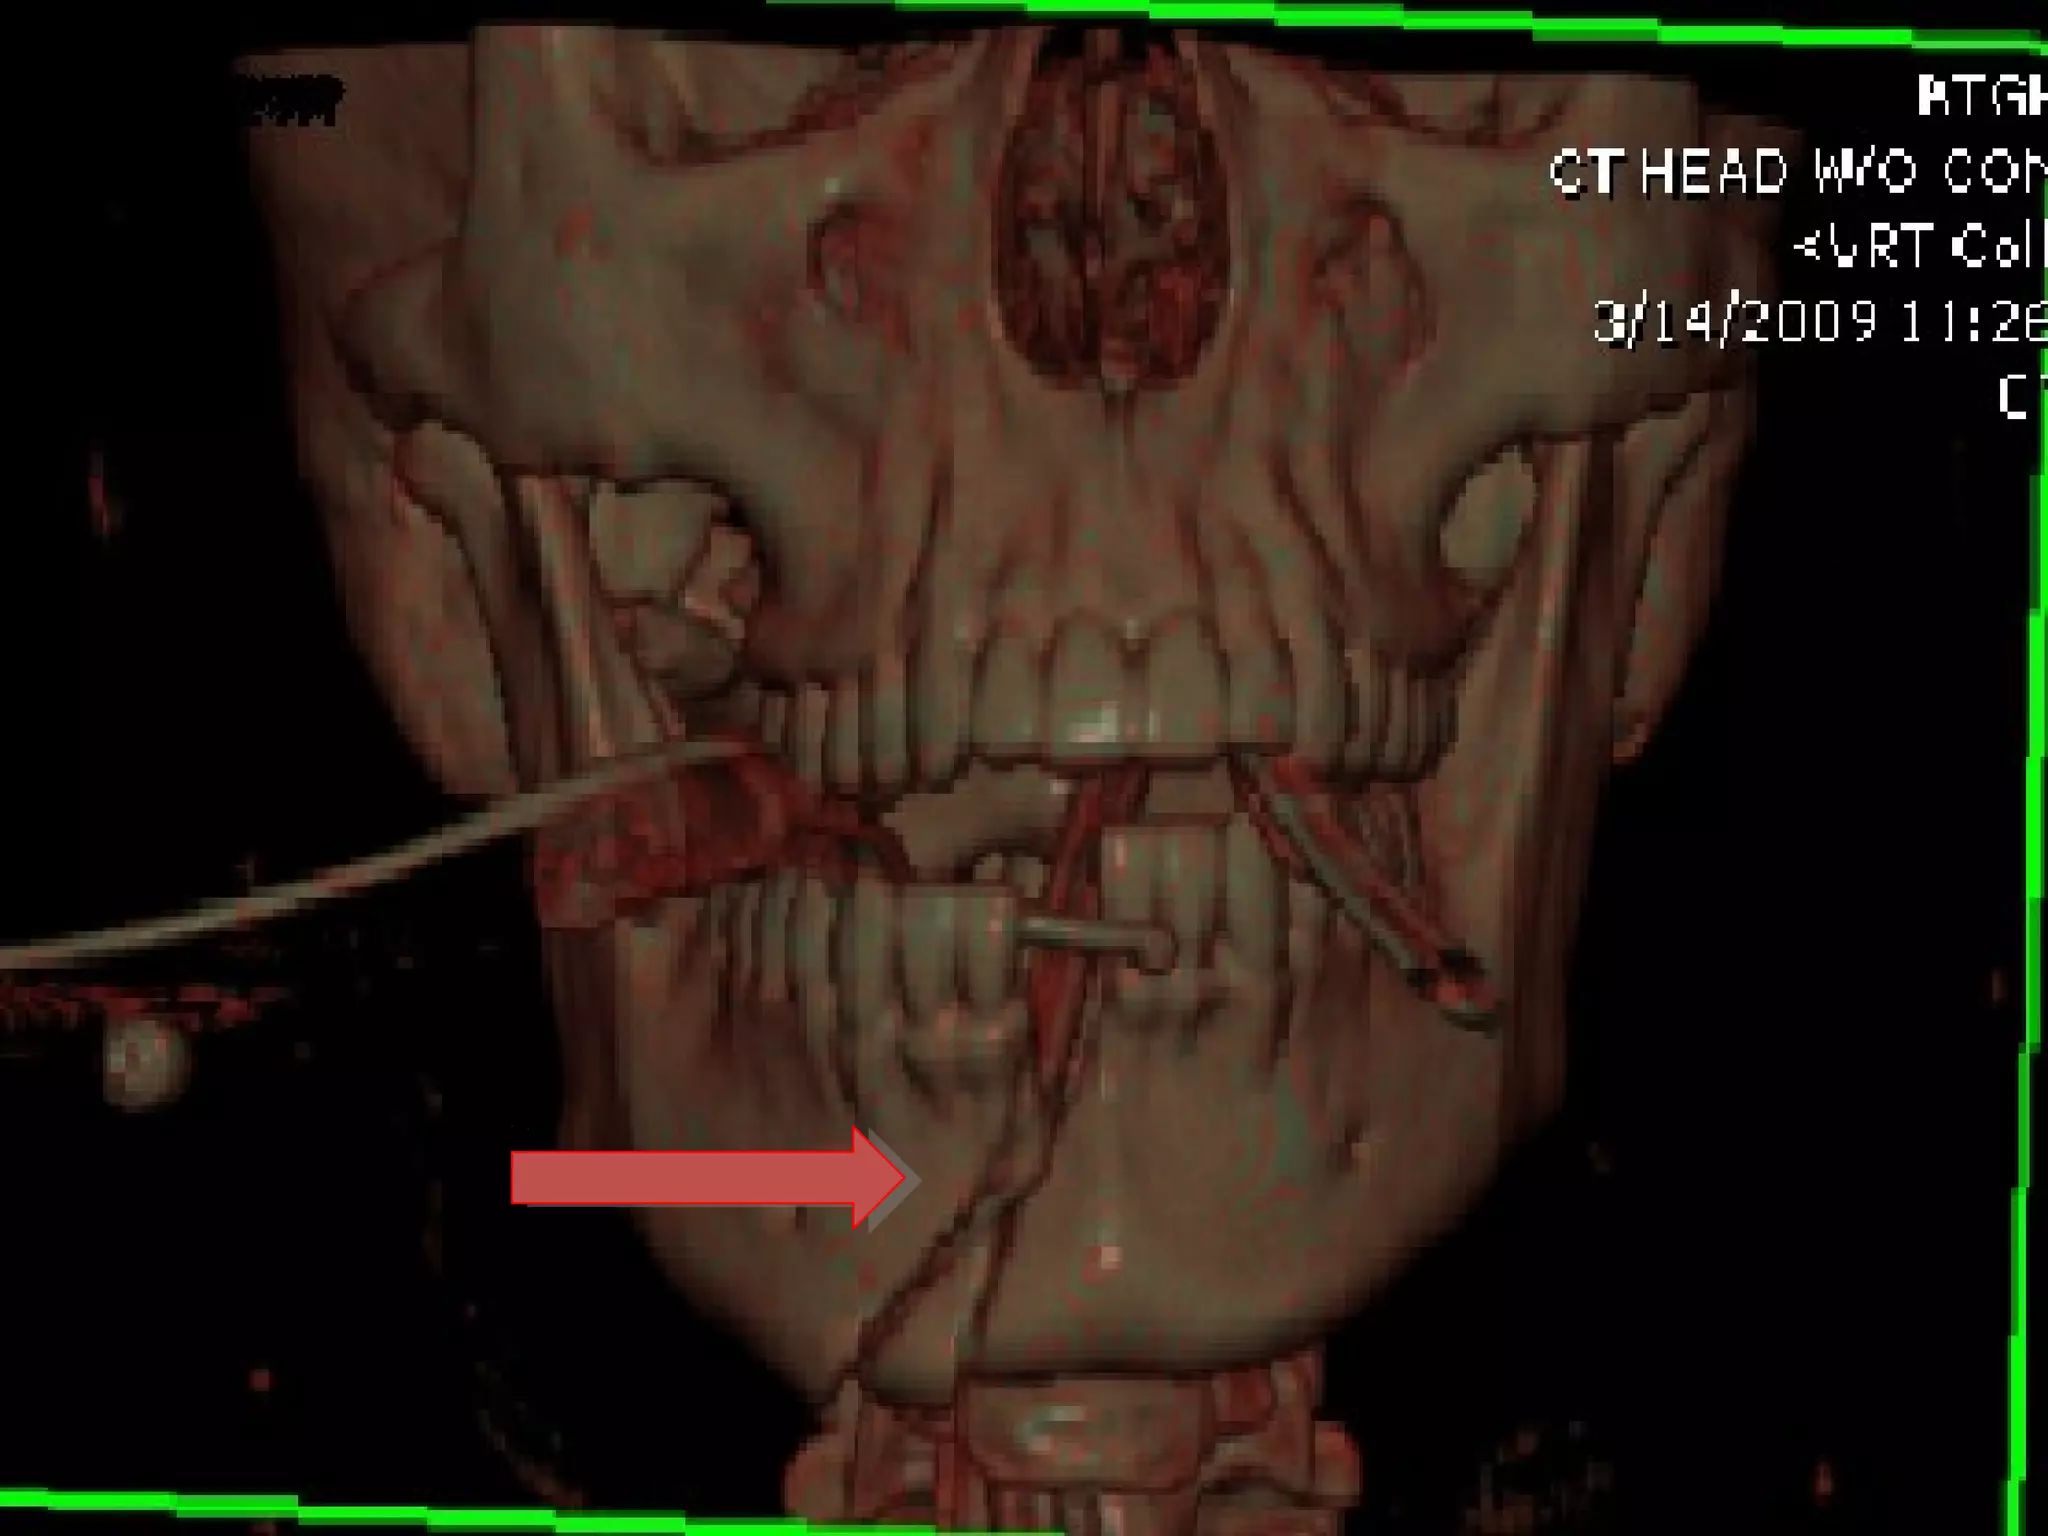

Computed Tomography (CT)

1. Also called CAT scanning or “CT”

2. X-Ray beam moves 360 around the patient

3. Consecutive x-ray “slices” around the patient

4. Computer can recreate 3D image of the body or

Image “slices” reconstructed by computation

5. Best for evaluating bone and soft tissue tumors,

fractures, intra-articular abnormalities, and

bone mineral analysis

• #54 Mandible fracture